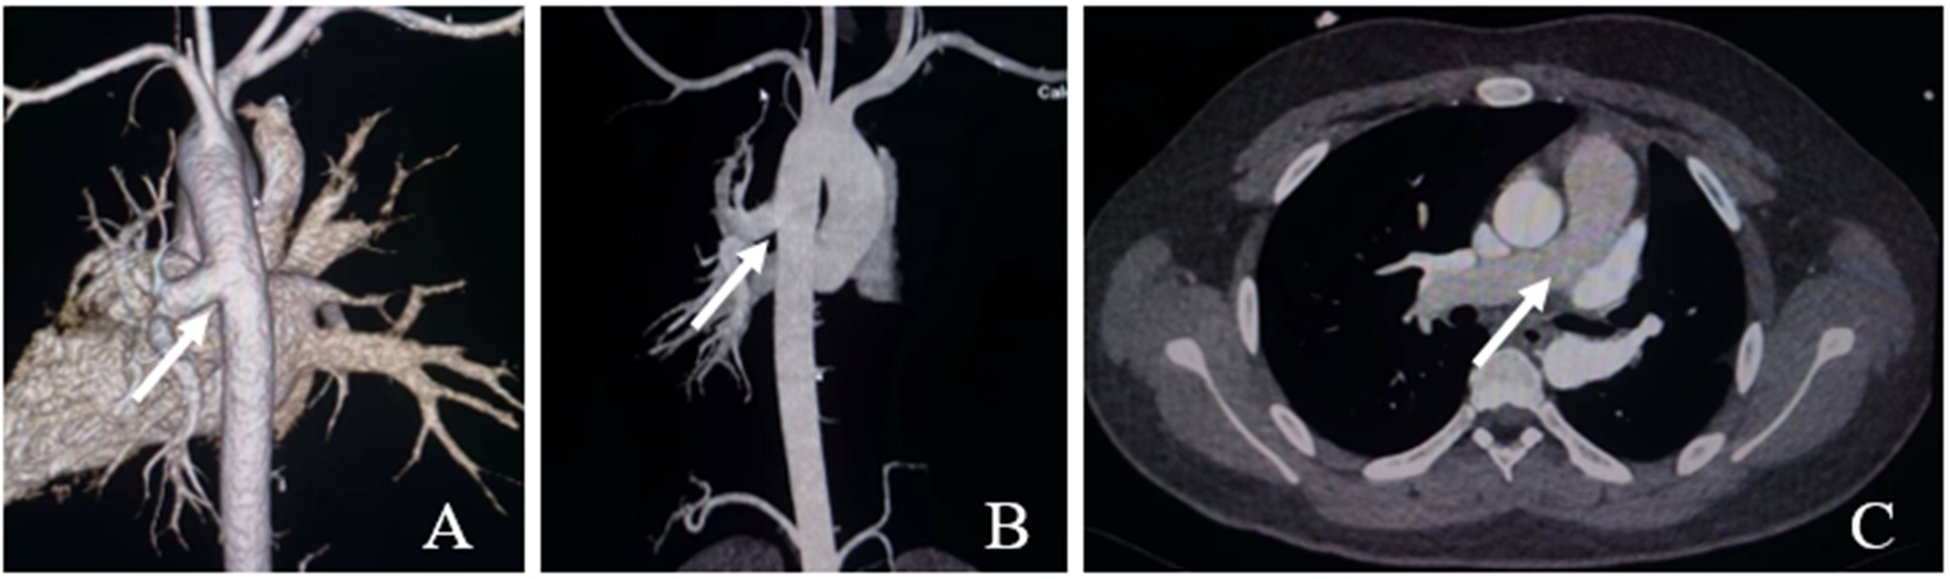

A 15-year-old male patient was admitted to our hospital in September 2022 because of hemoptysis following strenuous exercise around 4 years ago. The hemoptysis was bright red in color, about 5 ml each time, with aggravation for 2 months. He had no chest tightness, palpitations, cyanosis, or lower extremity edema. The patient showed no signs of systemic circulatory congestion and the right ventricular diameter was normal indicated by echocardiogram (Supplementary Material 1). Echocardiography revealed a branch of main pulmonary trunk to the right and moderate PH.; however, no left pulmonary artery branch was observed. Aortic CTA reported AOLPA from the thoracic aorta (Figure 1).

Figure 1. Ct aortic angiography. (A,B) The left pulmonary artery arises from the descending aorta (white arrow); (C) The main pulmonary artery continues directly into the right pulmonary artery (white arrow).

Physical examination: Well-developed with a height of 177 cm and weight of 90 kg. No cyanosis of the lips or deformity of the thorax was found. Heart rate was 72 beats/min, normal sinus rhythm No pathological murmur in any of the auscultatory valve areas, and resting finger pulse oxygen saturation was 98%. The right heart catheterization was performed and the mean pulmonary artery pressure was 15mmhg (Supplementary Material 2). Following the completion of various examinations, elective surgery was performed.

The preoperative discussion focused on two aspects. The first was the choice of surgical approach and method. The primary procedure for surgical treatment is to separate the pulmonary artery of anomalous origin from the aorta and then reconnect it with the main pulmonary trunk. Based on the results of the CTA and three-dimensional reconstruction technique, we found that the distance between the left pulmonary artery and the main pulmonary trunk after transection was too far to be directly anastomosed, and an artificial blood vessel was required to extend the pulmonary artery, followed by end-to-side anastomosis with the main pulmonary artery. However, due to the anatomical distance, it was difficult to deal with the descending aorta and the main pulmonary artery simultaneously under single incision. Therefore, we reached a consensus for a double-incision surgery of median sternotomy and left lateral thoracotomies. Nevertheless, attention should be paid to the pathophysiology associated with the pulmonary circulation. After the left pulmonary artery is reconnected to the main pulmonary artery, blood flow in the pulmonary circulation will be redistributed, potentially leading to hypoxemia. In addition, prolonged aortic blood supply to the left pulmonary artery may result in increased pulmonary artery resistance and slower pulmonary blood flow, increasing the risk of thrombosis in the pulmonary artery and artificial blood vessels. Therefore, we administered additional anticoagulant therapy for a certain period of time after surgery.